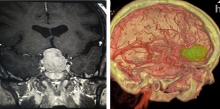

Imaging advancements, including 3D Doppler imaging to detect cancers in numerous organs, are used to accurately guide biopsies, target therapy and provide focused follow-up after treatment. ITN spoke with current editorial advisory board member Robert L. Bard, MD, PC, DABR, FASLMS, to find out more about recent advancements in diagnostic radiology. This video is Part 1 of a 3-part video series.

Dr. Bard is internationally known and recognized as a leader in his field. He specializes in advanced 3-D Doppler imaging to detect cancers in numerous organs, including the breast, prostate, and other areas. His images are used to accurately guide biopsies, target therapy and provide focused follow-up after treatment. He is committed to improving non-invasive cancer testing and developing minimally invasive image guided technologies to prevent cancer spread.